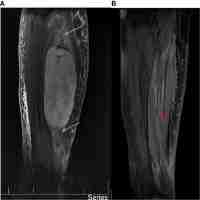

| Abstract | Background To report our early experience with carbon ion irradiation in the treatment of gross residual or unresectable malignant peripheral nerve sheath tumors (MPNST). Methods We retrospectively analysed 11 patients (pts) with MPNST, who have been treated with carbon ion irradiation (C12) at our institution between 2010 and 2013. All pts had measurable gross disease at the initiation of radiation treatment. Median age was 47 years (29-79). Tumors were mainly located in the pelvic/sacral (5 pts) and sinunasal/orbital region (5 pts). 5 pts presented already in recurrent situation, 3 pts had been previously irradiated, and in 3 pts MPNST were neurofibromatosis type 1 (NF1) associated. Median cumulative dose was 60 GyE. Treatment was carried out either as a combination of IMRT plus C12 boost (4 pts) or C12 only (7 pts). Results Median follow-up was 17 months (3-31 months). We observed 3 local progressions, translating into estimated 1- and 2-year local control rates of 65%. One patient developed distant failure, resulting in estimated 1- and 2-year PFS rates of 56%. Two patients have died, therefore the estimated 1- and 2-year OS rates are 75%. Acute radiation related toxicities were generally mild, no grade 3 side effects were observed. Severe late toxicity (grade 3) was scored in 2 patients (trismus, wound healing delays). Conclusion Carbon ion irradiation yields very promising short term local control and overall survival rates with low morbidity in patients suffering from gross residual or unresectable malignant peripheral nerve sheath tumors and should be further investigated in a prospective trial. |